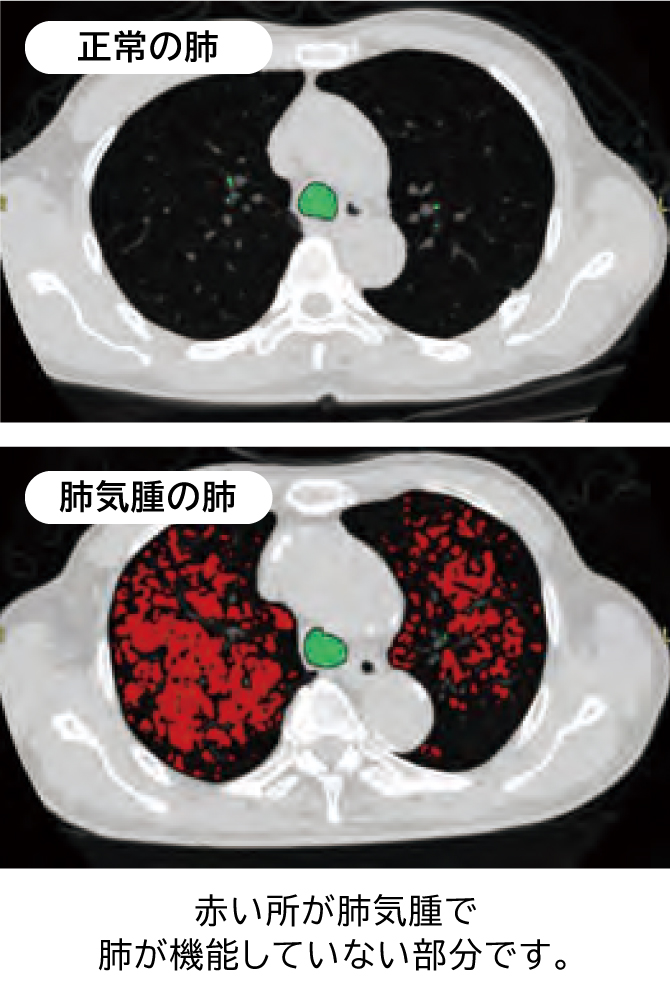

肺気腫と慢性気管支炎を含めた肺疾患の総称をCOPD(慢性塞栓性肺疾患)といいます。

これはタバコなどの有害な空気を吸い込むことで肺に炎症が起こり、呼吸障害を引き起こす進行性の病気です。

症状が進むと少し動くだけで息苦しくなり、酸素吸入が必要になるなど日常生活に大きな支障をきたします。

この検査で現在の肺気腫の進行度を知り、COPDの予防につなげていきましょう。肺がんCTとセットの検査です

この検査は肺気腫の進行度を画像化して調べる検査です。

肺がんCT検査とセットで行いますが、撮影時間は通常のCT検査と変わりません。注意事項